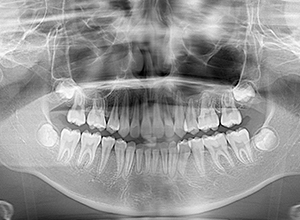

FP・IOP

X-Ray

主訴 出っ歯 診断名 アングルⅡ級1類

初診時年齢 10歳2ヵ月 性別 動的治療期間 23ヵ月

口腔内所見 大臼歯関係は右側がエンドオンのclassⅡ、左側がfull classⅡ。 上顎正中は下顎正中に対して僅かに右側偏位しており、上顎前歯は大きく唇側傾斜しover jetが11.0mmと上突咬合を呈していた。また下顎歯列の緩やかなスピーカーブのため過蓋咬合(over biteは5.0mm)となっていた。

X-Ray所見

セファロ所見 下顎骨はしっかりとしているが顎顔面の奥行きに比べて下顔面高さが低い。頭蓋に対して上顎骨は前方位にあり、上下顎骨の前後的位置関係のズレは大きかった。